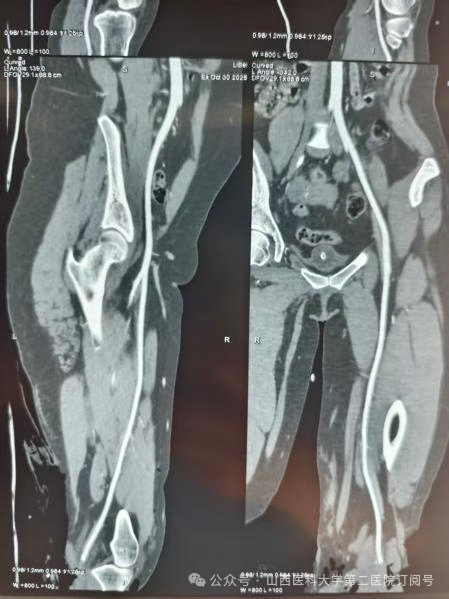

患者不慎在十字路口被右拐挂车剐蹭摔倒,致使左小腿中段被半挂车轮大力碾压,左胫腓骨完全性、毁灭性缺损,软组织条件极差,左下肢仅剩不到四分之一的皮肤与身体相连,其余肌肉骨骼难觅其踪,左膝以下动脉已被闭塞血供消失。不幸中的转机是患者左踝以下保存完好,踝关节面未见明显损伤,因严重外伤导致左小腿胫腓骨完全性、毁灭性缺损,软组织条件极差。按照常规诊疗思路,如此严重的损伤,截肢或许是“最稳妥”的选择。但截肢意味着患者将永久失去左膝以下肢体,未来的假肢适配、步态训练、心理创伤都是漫长而艰辛的过程。经过张桦栋医师团队严谨的术前讨论和精密的设计,一个大胆而富有创造性的手术方案被最终确定:左下肢旋转成形术。

骨科总住院医师张桦栋医师介绍:“这个手术的理念堪称重塑。其核心原理是将受损严重的左小腿部分及左膝切除,保留功能完好的足部,并将其旋转180度后,与大腿股骨进行固定融合。这样一来,原本的踝关节就扮演起了膝关节的角色。形象地说,这就像进行了一次精密的“人体拼装”:将脚踝调转方向,与大腿连接。术后,通过专业的康复训练,患者可以利用这个“新的膝关节”(即原来的踝关节)进行屈伸活动,从而驱动假肢,实现更自然、更有力的行走。这远比传统大腿截肢后佩戴的假肢功能更优,能量消耗更少,步态也更接近正常人。